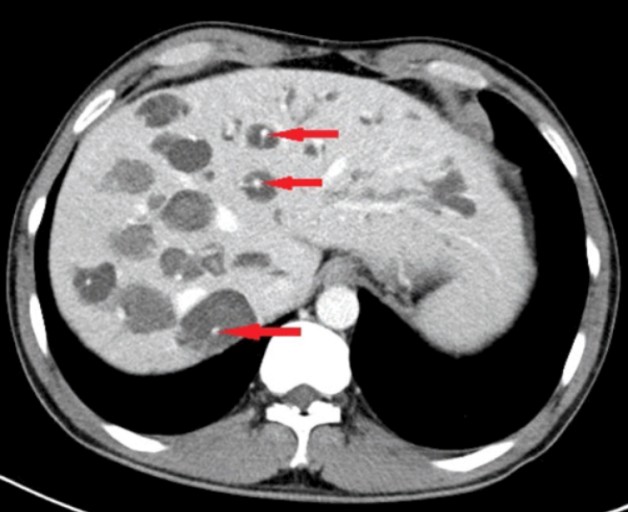

간낭종은 간에 발생하는 양성 종양입니다. 물혹처럼 생겼으며, 대부분 무증상으로 진행됩니다. 드물게 증상이 나타나기도 하지만, 일반적으로 치료가 필요하지 않습니다. 간낭종은 전 연령대에서 발생할 수 있고, 여성에게 조금 더 흔합니다.